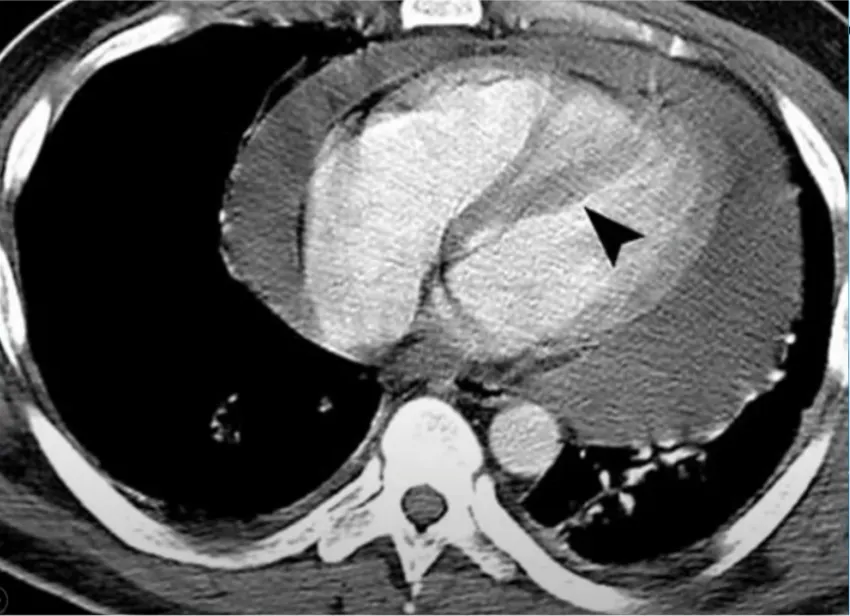

Parasternal technique

가장 가까운 위치이나 proximal LAD puncutre의 위험이 있고, internal mammary artery/intercostal vessel injury의 위험성이 있음

•

5,6번째 갈비뼈 위 경계선이자, Sternum margin 바로 옆에 needle insertion

피부에 직각으로 들어가야 함

Sternum margin에서 1cm 이상 옆으로 가게 되면 internal mammaryh vessel injury의 위험

Rt.parasternal technique 도 사용할 수 있음

이 CT 의 case를 보면, apex와 Lt.paraternal 접근이 쉽지 않았음

->Rt.parasternal 통해 쉽게 해결하였던 케이스